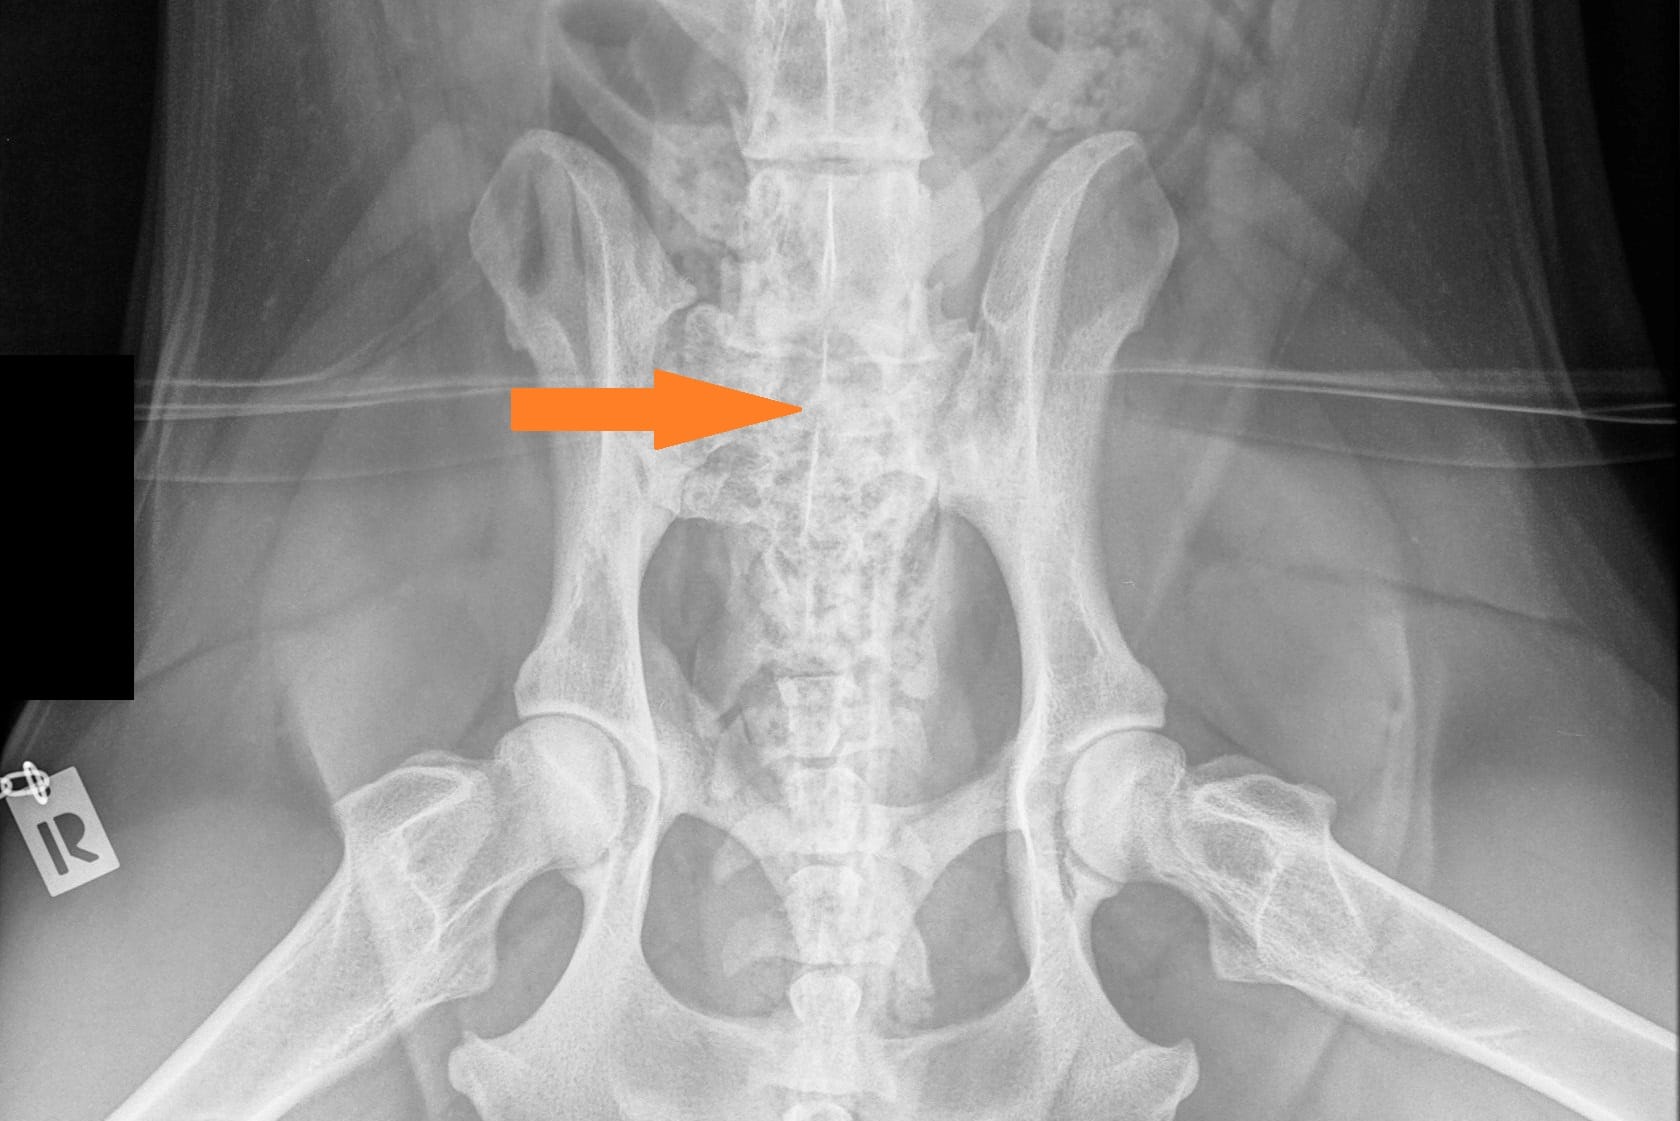

Lumbosacral transitional vertebra (LTV) in Rhodesian Ridgebacks

LTV3_VD_ARR-3

LTV2_VD_ARR-1